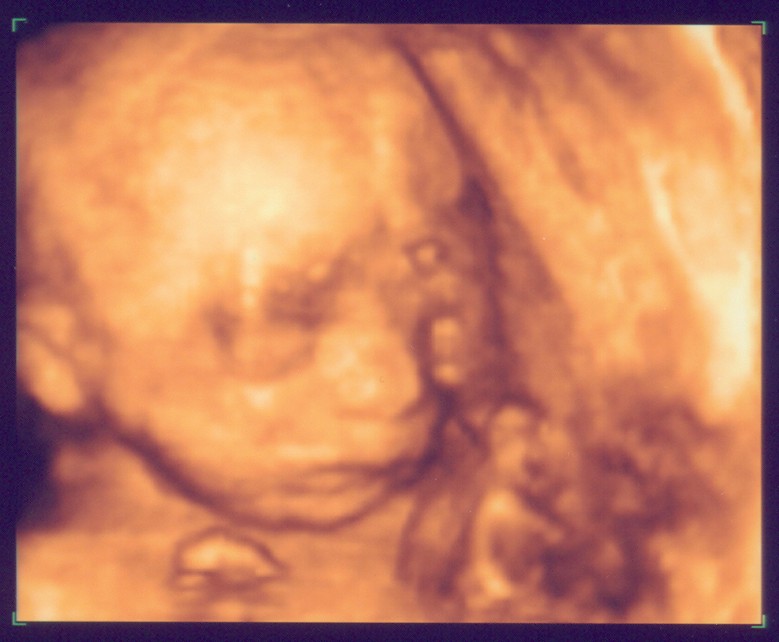

Rechtes Kind im 3D-US

Sorry, dass ich euch bis heute auf die Folter gespannt habe, aber: Nun hat das Warten hat ein Ende ES GIBT NEUE FOTOS!!!

Ist ja echt Wahnsinn, was heute technisch so alles machbar ist. Wir waren übrigens im Klinikum Kassel bei Dr. Simoens. Wenn die Möglichkeit besteht, kann ich das nur empfehlen. Die Wartezeit war extrem kurz und der Doc war sehr nett. Darüber hinaus hat er im Untersuchungszimmer zwei zusätzliche riesige Bildschirme damit sowohl Mann als auch Frau alles sehen können. Echt Klasse.

Hintergrund der Untersuchung war - so die normale Gyn - dass sie bei Mehrlingsschwangerschaften grundsätzlich ein Fehl-/Missbildungs-Sono machen lässt. Soweit es im US ersichtlich war, ist glücklicher Weise alles in Ordnung.

Eure Bilder sind echt toll. Wenn ich mich jetzt nicht allzu blöd anstelle, seht Ihr gleich das aktuellste von unserem Baby. Mit 3-D kann man schon sehr schön alles erkennen, aber wir haben auch ganz schaurige Bildchen. Kommt immer darauf an, wie die Mäuse posieren. :wink: